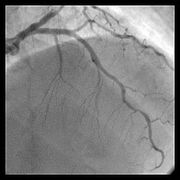

冠状动脉造影术的操作技巧- 4.8共8页

- 冠状动脉造影术的操作技巧姓名:考号:一、单选题(共10题)1在进行冠状动脉造影术时,正确的导管插入位置是A股动脉B股静脉C静脉D动脉2冠状动脉造影术中最常用的造影剂是什么A生理盐水B碘对比剂C葡萄糖D肝素3在进行冠状动脉造影术时,导管推进的技巧是什么A快速推进,避免损伤血管B缓慢推进,避免损伤血管C逆时针旋转推进